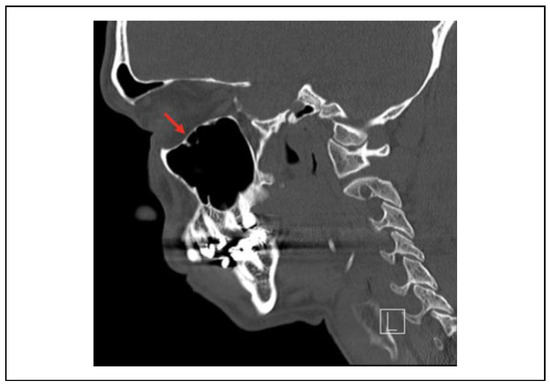

Indications and Timing of Repair

Delayed Repair

Approach